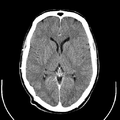

تصوير مقطعي حاسوبي

التصوير المَقْطَعي الحاسوبيX-ray computed tomography نظام تصوير بالأشعة السينية، يُسْتخدم لتصوير مختلف أجزاء الجسم مثل الرأس والقلب والبطن. ويستعين الأطباء بالتصوير المقطعي الحاسوبي على تشخيص الأمراض وعلاجها. وتسمى هذه التقنية أيضًا التصوير المقطعي المحوسب أو التصوير المقطعي المحوري المحوسب.

معرض الصور